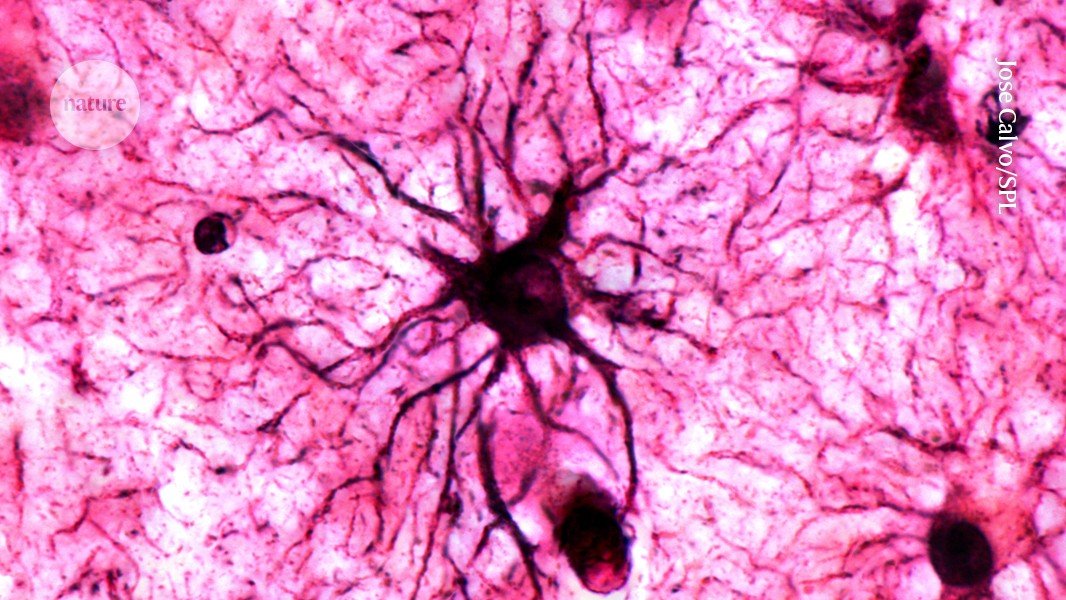

A type of brain cell called astrocytes play a crucial role in stabilizing memories in the brain.Credit: Jose Calvo/SPL

Why are we able to remember emotional events so well? According to a study published today in Nature1, a type of cell in the brain called an astrocyte is a key player in stabilizing memories for long-term recall.

Astrocytes were thought to simply support neurons in creating the physical traces of memories in the brain, but the study found that they have a much more active role — and can even be directly triggered by repeated emotional experiences. The researchers behind the finding suggest that the cells could be a fresh target for treating memory conditions such as those associated with post-traumatic stress disorder and Alzheimer’s disease.